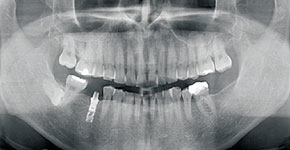

広範囲の撮影が可能なCT(3D撮影)機器です。3D撮影によって多角的な診断が実現し、親知らずの抜歯やインプラント治療、根管治療などの複雑な治療を安全・正確に行うことができます。デジタル方式を採用しているため低被ばくで、被ばく量は従来の機器と比べて大幅に減少しています。

パノラマレントゲン(2D)撮影